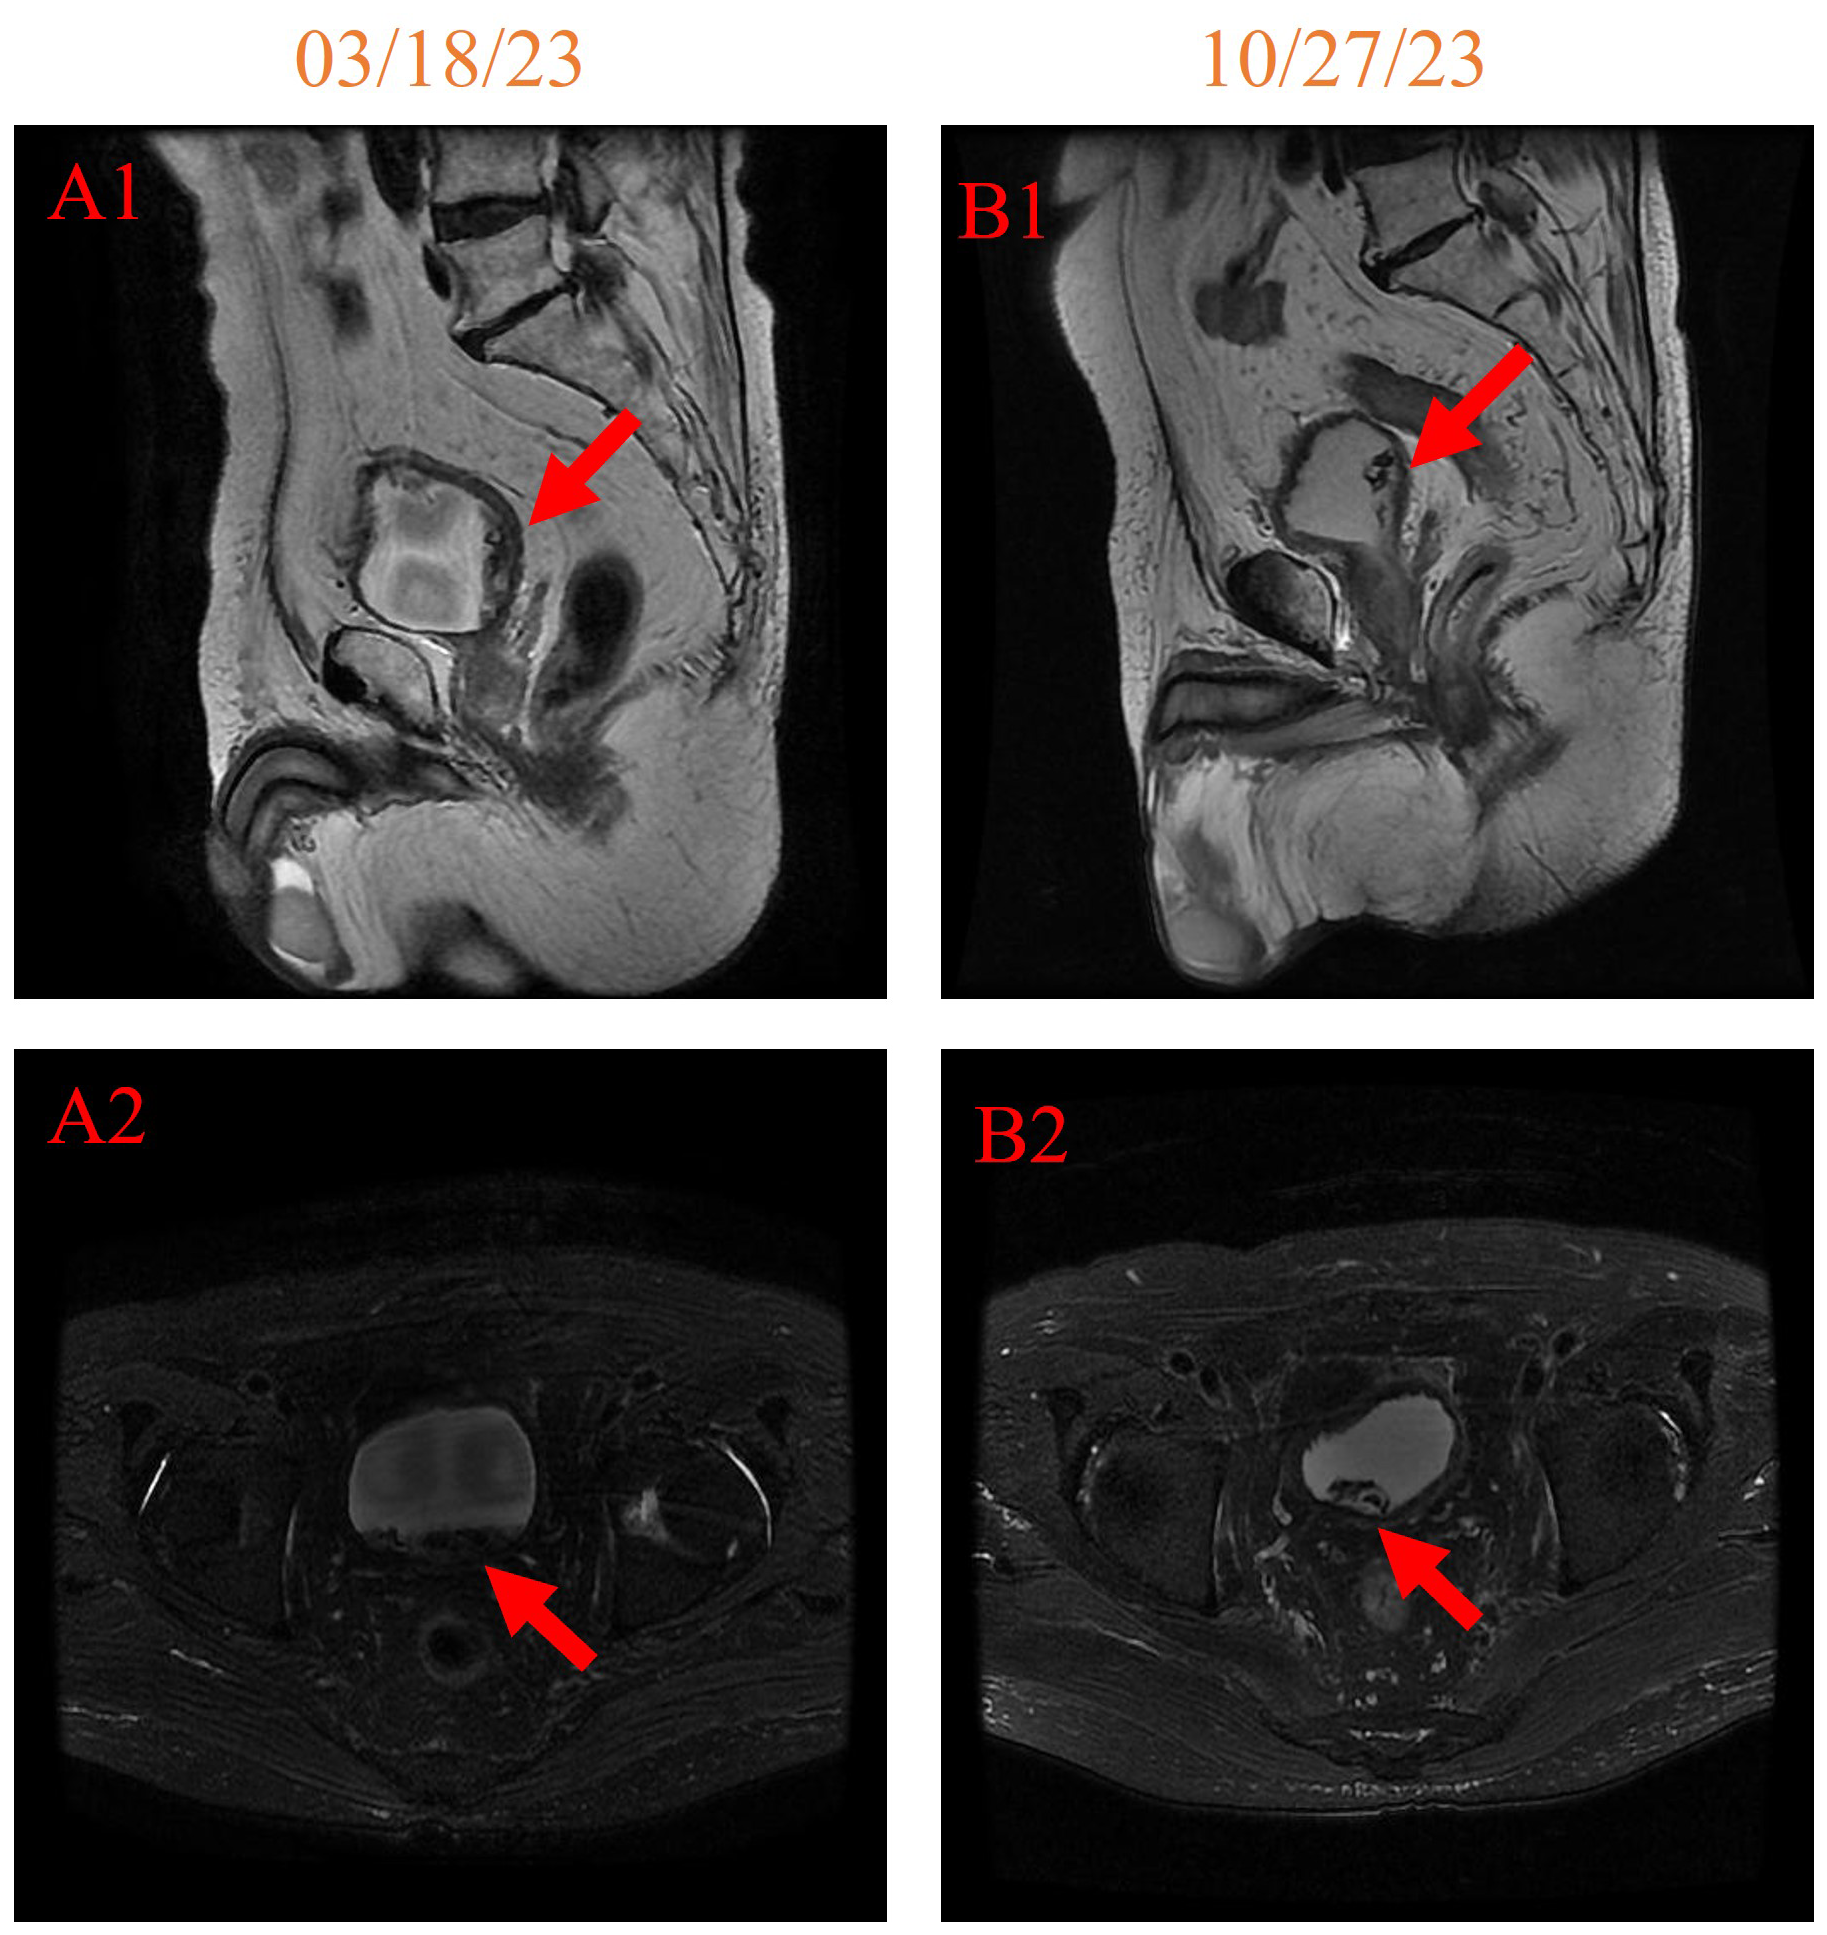

In addition, notable improvements were observed when comparing the pelvic MRI on 27 October 2023 with that on 18 March 2023 (Figure 4). The space occupied by the left posterior wall of the bladder shrank, and the hemorrhage in the bladder cavity has also reduced. These findings collectively indicate positive progress in the patient’s pelvic region.

Figure 4. pelvic MRI imaging on 18 March 2023 [(A1, A2) 158 days after initiating HBOT] and 27 October 2023 [(B1, B2) 381 days after initiating HBOT].